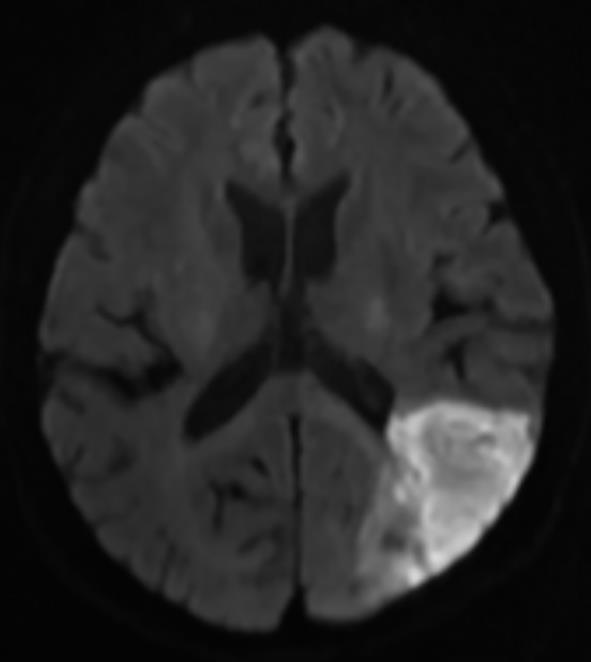

摘要:目的 探讨急性脑梗死(ACI)中磁共振弥散加权成像(MRI DWI)特征在血管内血栓切除术(EVT)后颅内出血的预测价值。方法 将2021年8月—2023年12月在宣城市人民医院行EVT治疗的ACI患者107例纳入研究。根据EVT后有无颅内出血分组,收集患者一般资料,计算DWI梗死体积及最大达峰时间(Tmax)。结果 两组患者从发病到入院、EVT及静脉溶栓时间等比较,差异无统计学意义(P>0.05),但术后颅内出血组空腹血糖(FBG)、糖化血红蛋白(HbAlc)水平及DWI值高于无出血组(P<0.05)。HbAlc、FBG、DWI梗死体积是预测ACI患者EVT后出血的预测因子(P<0.05)。结论 ACI中MRI DWI特征、FBG和HbA1c可作为EVT后颅内出血的预测指标,与术后颅内出血发生风险相关。